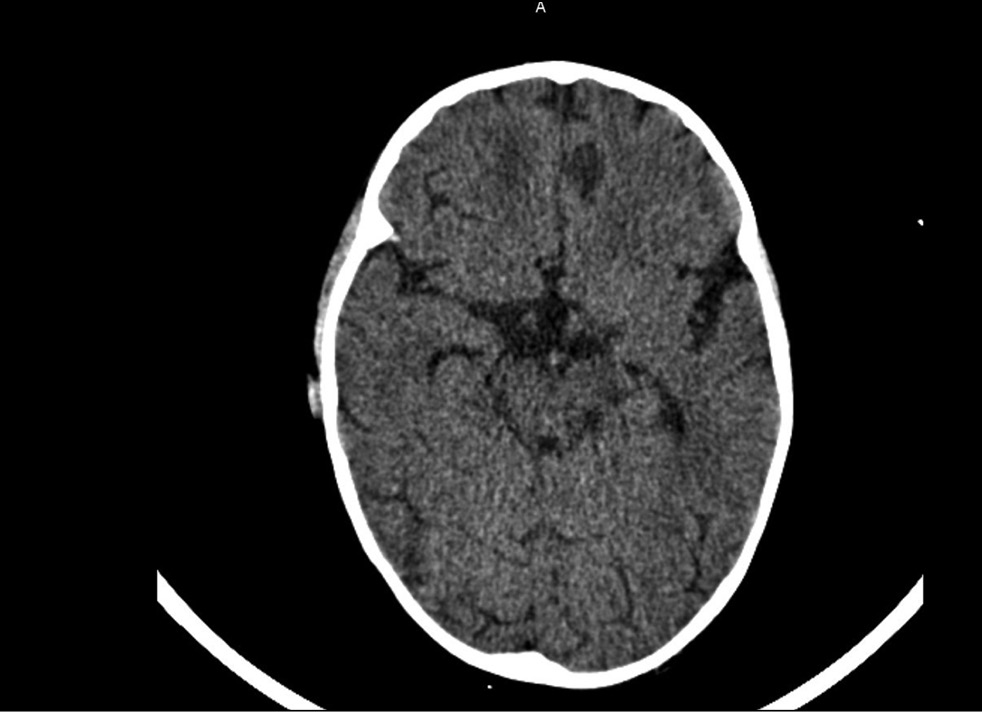

Повторная РКТ на 20-й день госпитализации показала признаки множественных очагов деструкции медиальных стенок орбит, костей носовой полости, твёрдого нёба, альвеолярных отростков верхнечелюстной кости, дефект мягкого неба. Таким образом, было больше данных, свидетельствующих о некротических изменениях, субпериостальный абсцесс крылонебной ямки и орбиты (рис. 2). Появился гиподенсивный очаг в правой лобной доле (энцефалит?) (рис. 3).

Рис. 2. Рентгеновская компьютерная томография орбит, придаточных пазух носа, головного мозга на 20-й день госпитализации.

Fig. 2. X-ray computed tomography of the orbits, paranasal sinuses, and brain on day 20 of hospitalization.

Рис. 3. Рентгеновская компьютерная томография головного мозга с очагом на 20-й день госпитализации.

Fig. 3. X-ray computed tomography of the brain with a focus on the day 20 of hospitalization.